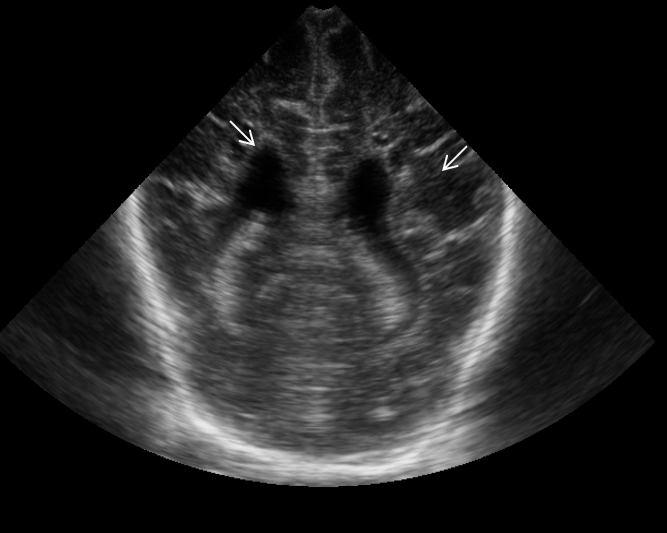

Neonatology Grade 4 PVL 3 Image